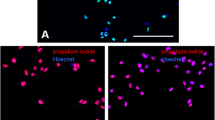

Figure 1a illustrates the schematic representation of the differentiation procedure and the morphology of cells at different stages. According to the protocol that reported previously (Peymani et al. 2017; Pouya et al. 2011), hESCs were passaged at start point and cultured to form EBs (Stage 1). At the next stage, the induction of neuroglial differentiation was performed by treating with retinoic acid (RA; Sigma) for nine days (Stage 2). This process results in the appearance of yellow spheres. Cellular proliferation step started after removal of RA, and yellow spheres were cultured in EGF supplemented GRM with for next 18 days. In this stage, the size of EBs increased (Stage 3). On day 28 from the starting point, free-floating spheres were plated on matrigel followed by adherence of EBs. The differentiated cells started to migrate outward from the plated spheres and were proliferated in the culture. Morphology of these cells was similar to immature bipolar and multipolar OPCs (Stage 4). To estimate OLs maturation, EGF was removed from the medium and cells were re-plated on poly-L-laminin (PLL)/Lam (laminin) substrate for three weeks. Ultimately, plated cells displayed oligodendroglial morphology (stage 5) (Fig. 1a). Differentiated bipolar cells obtained from stage 4 were analyzed by immunofluorescence staining for expression of typical markers of OPCs. As previously described, expression of the OPCs markers, A2B5 and PDGFRα, was evident in the cell while no GFAP-positive cell was detected. Also myelination was observed in OLs (Peymani et al. 2017; Pouya et al. 2011). Additionally, RT-qPCR for OLIG2 and PDGFR confirmed the recent data obtained by immunostaining (Fig. 1b). Data confirmed appropriate OPCs induction in this study.

Flow cytometry assessments indicated that OPN prevented inductive effects of H2O2 mediated induced caspase activation. Caspase activity assay in untreated cells (a) was compared with treated OPCs with H2O2 (3200 μM) in ± OPN (12.5 ng/mL) (b, c). As shown, activity of caspase 3 was low in untreated OPCs (approximately 14%, a), while H2O2 treatment induced this activity significantly (approximately 92%, b). Interestingly, OPN pretreatment remarkably decreased the rate of caspase 3 activation near to 58% (c)